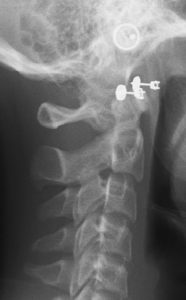

A 12.5 year old caucasian female presents with the chief concern that “My front teeth stick out.”